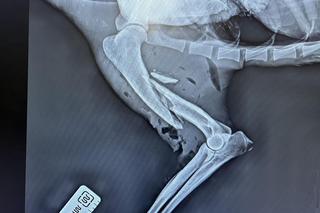

Zwierzę było niestety w bardzo złym stanie: kikut prawej kończyny – najprawdopodobniej amputowana przez wpadnięcie w kłusownicze wnyki – oraz uraz lewej przedniej kończyny sprawiły, że organizm wilka był dodatkowo destrukcyjnie wyniszczony poprzez brak możliwości polowania i zdobywania pożywienia – relacjonuje załoga LCMZ.

Właśnie ten czynnik zadecydował o ponurym zakończeniu wilczej historii – kiedy wykonano badania i oszacowano możliwości życiowe, decyzja mogła być tylko jedna: eutanazja. Ciało zwierzęcia przekazano Poleskiemu Parkowi Narodowemu do dalszych badań.